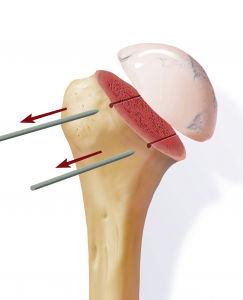

Anschließend wird der zerstörte Oberarmkopf entlang der Schnittlinie mit Hilfe einer Resektionslehre entfernt (Abb. 39). Mit einer Bohrschablone wird das Einbringen der Hohlschraube vorbereitet (Abb. 40) und die definitive Prothesengröße bestimmt. Nun kann bei freier Sicht auf die Gelenkspfanne selbige ausgetauscht werden, sofern dies aufgrund fortgeschrittener Erkrankung nötig ist (Abb. 41).

Daraufhin wird der Kalottenträger mittels der selbstschneidenden Hohlschraube im Oberarmschaft befestigt. Nun wird der endgültige Prothesenkopf angebracht (Abb. 49).